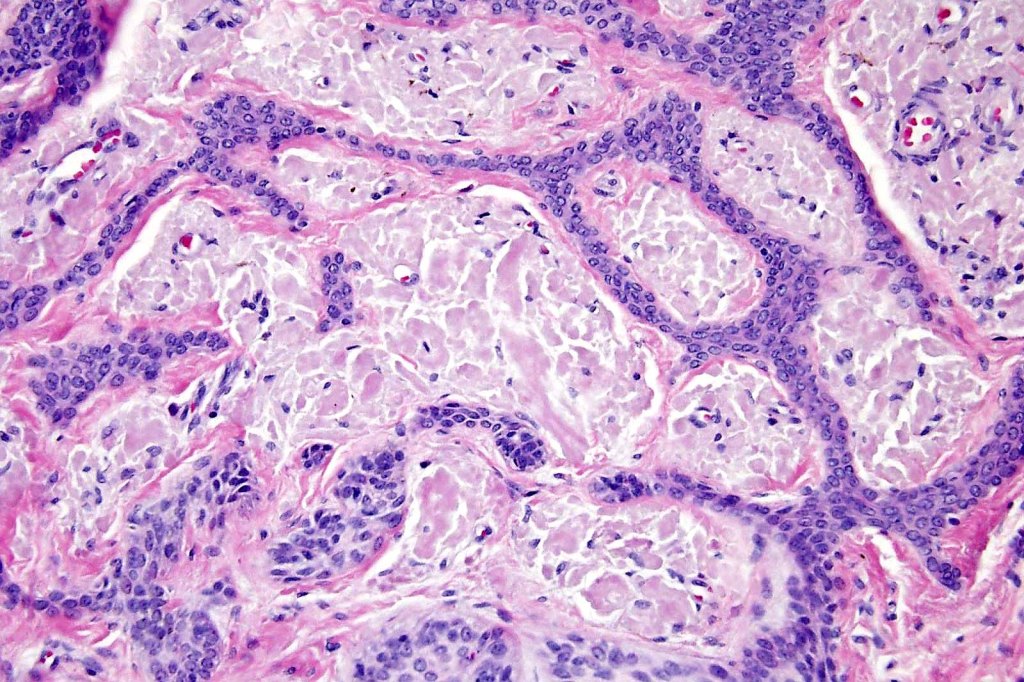

Histological features

•Anastomosing basaloid, narrow epithelial strands associated with a prominent fibrous (sometimes myxoid) stroma

•Peripheral palisade

•Round to oval vesicular nuclei with small nucleoli

•Mitoses very scanty or absent

•Hair germs sometimes present

•CK20 +ve Merkel cells almost invariably present